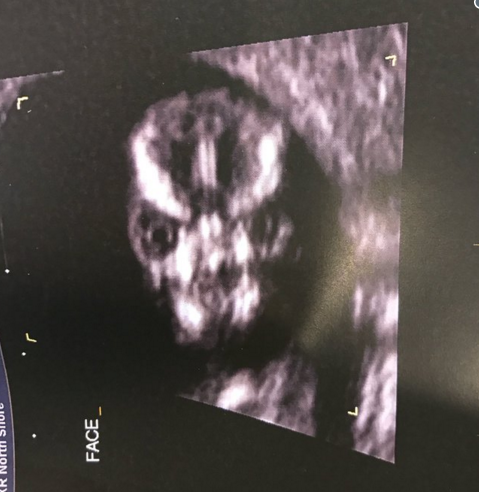

Trudnica Šarni Tarner objavila je na Tviteru fotografiju ultrazvuka svoje bebe kojom je šokirala javnost. Naime, na ultrazvuku bebina glava izgleda kao mrtvačka lobanja.

– Tehničar na ultrazvuku odlučio je da napravi snimak lica deteta s prednje strane i to je najstrašnija stvar koju sam u životu videla – napisala je ona na Tviteru.

Ona se na takve neumesne komentare nije obazirala, već je samo objasnila da tako zapravo ljudska lobanja izgleda na snimcima ultrazvuka.

Pogledajte fotografiju: